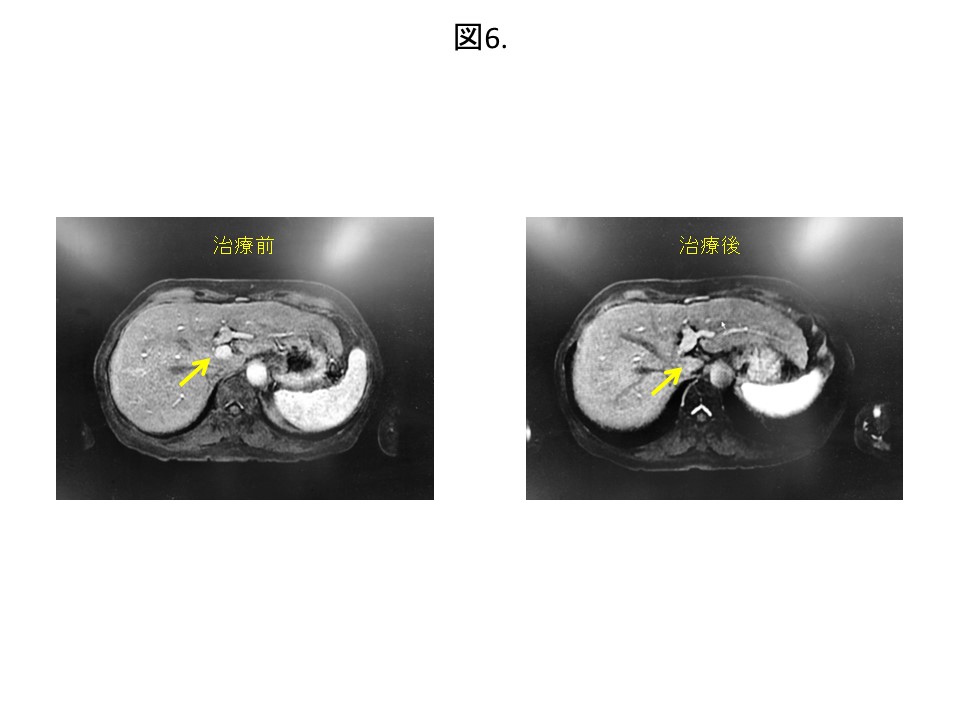

●肝細胞癌78歳女性:肝臓のS1と呼ばれる標準治療(手術・ラジオ波焼灼療法)が難しい場所に肝細胞癌を発症しました。当初は高難度の手術を受ける予定でしたが、体への負担が少なく安全に治療可能なサイバーナイフを選択されました。治療後、肝細胞癌は消失しました(図6)。治療から5年以上再発なく経過しています。